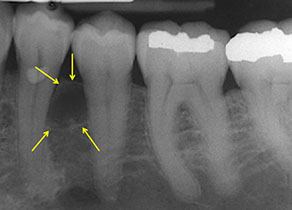

Keratocystic Odontogenic Tumor (KCOT)

- previously odontogenic keratocyst (OKC) but renamed 2/2 potential for aggressiveness, recurrence and genetic abnormalities

Parakeratin lined cyst-like tumor in bone (posterior mandible), ~1/10 of odontogenic cysts, MC up to 30 yo; 9/10 solitary

- multiple tumors assoc c Gorlin syndrome (nevoid basal cell carcinoma syndrome [NBCCS])

- may arise from dental lamina; usually cause jaw swelling

- grossly has thin wall c unerupted tooth

Micro: uniform epithelium of palisading hyperchromatic basal cell cuboidal to columnar cells w/o rete ridges

- luminal side c wavy "corrugated" parakeratotic epithelial cells and can have keratotic debris inside

Genes: 2-hit mech in bi-allelic loff of PTCH ("patched") tumor suppressor on 9q22.3 causing dysregulatio nof p53 and cyclin D1 oncoproteins

Tx: decompression , enucleation, excision (may be excessive)

Px: up to 1/2 recur (possibly 2/2 daughter cysts in the wall that are not excised, or fragmentation of the cyst wall during excision)